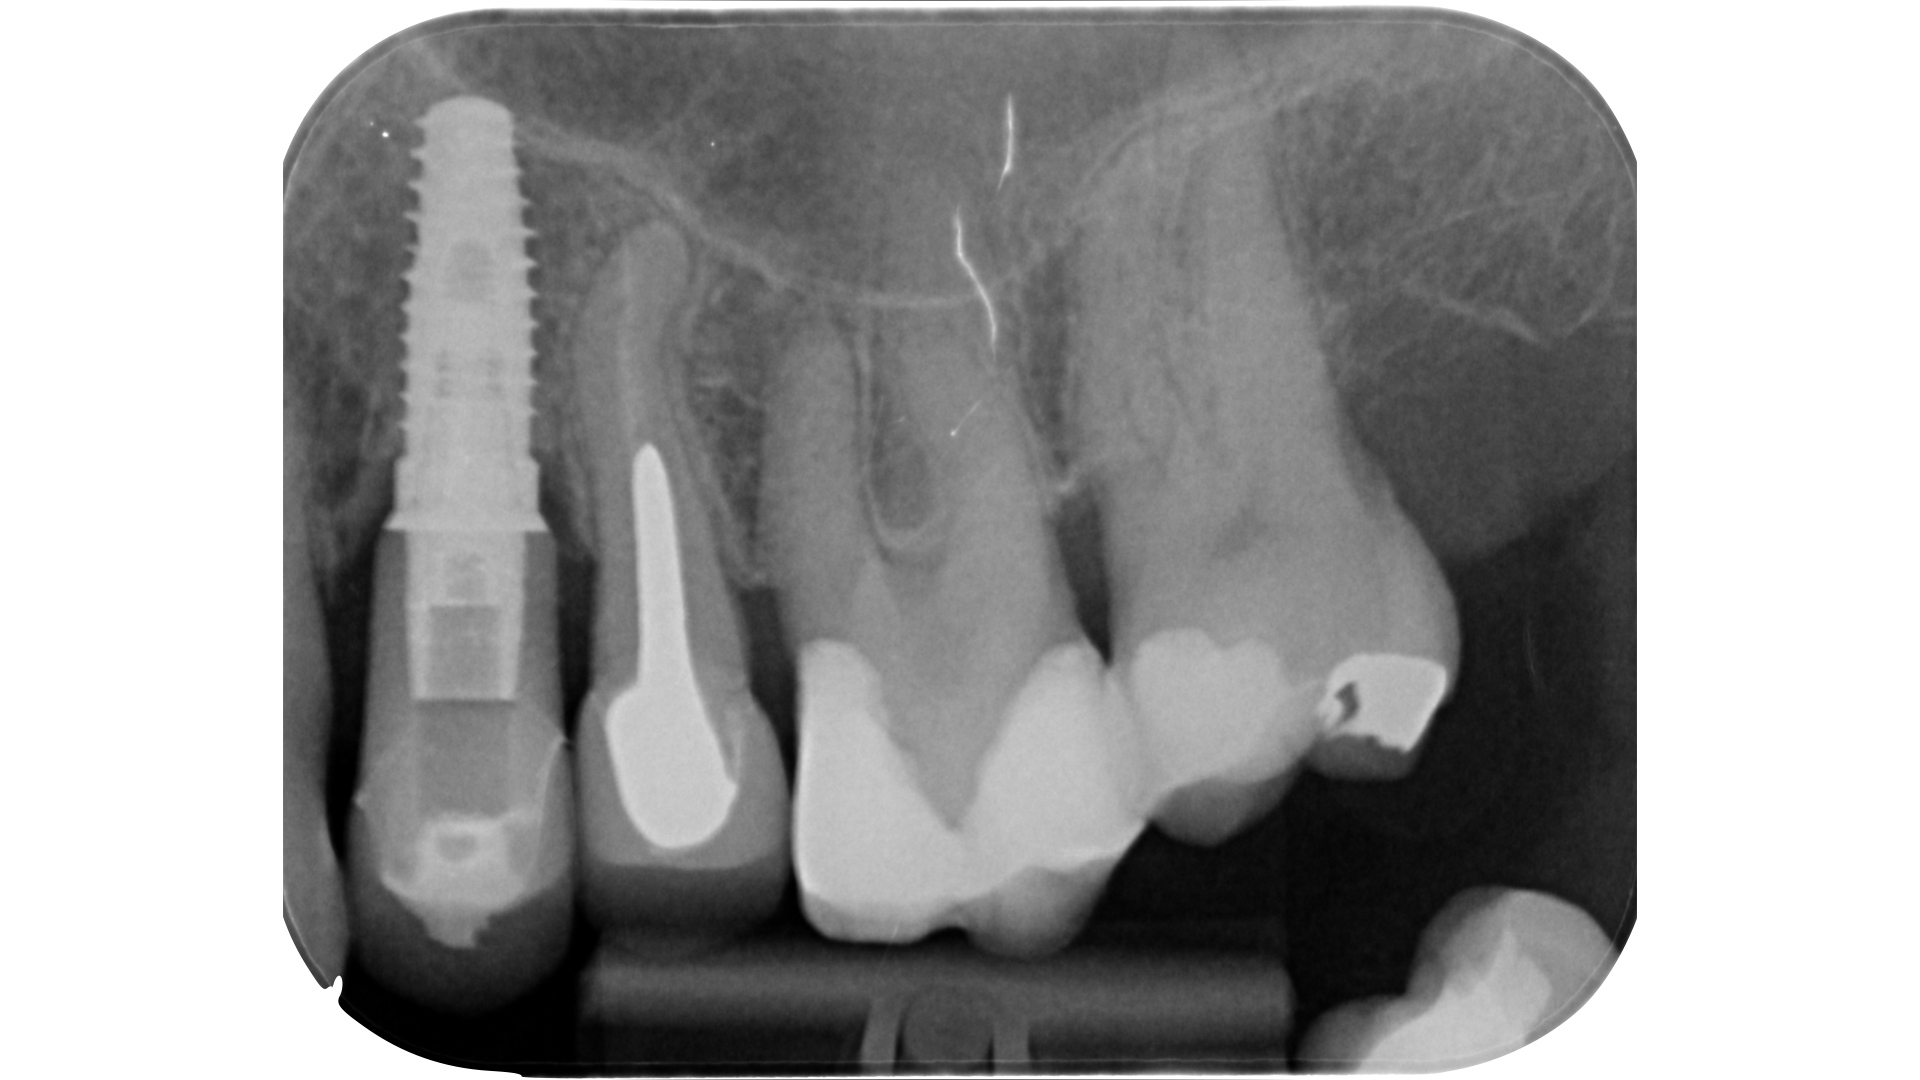

Il pavimento della camera pulpare si presenta sempre con un aspetto più scuro ed opaco rispetto al tessuto calcificato che tende ad essere lucido con un effetto che potremmo definire “vetrificato” (Figure 15-20).

Talvolta la differenza è evidente, in altri casi molto più sottile e quindi anche le difficoltà incontrate possono essere maggiori.

Asciugare la camera pulpare è il primo passaggio da compiere per poter visualizzare in modo netto le differenze.

A seguire l’utilizzo alternato di vari dispositivi a secco a bassi giri permette di distaccare ed eliminare i residui calcificati.

A seconda delle dimensioni e della localizzazione uno o più di questi dispositivi saranno sufficienti per dislocare e rimuovere i calcoli pulpari. In questa fase è molto utile eseguire lavaggi ripetuti con ipoclorito di sodio a cui far seguire un’accurata asciugatura per poter visualizzare i progressi compiuti e proseguire in modo sempre più preciso.

Lo step successivo, ossia l’esplorazione manuale e meccanica del sistema canalare, potrebbe nei casi più complessi essere impedito a causa dell’ostruzione dell’orifizio. Una calcificazione che si estende più in profondità rispetto al pavimento della camera pulpare può infatti rendere impossibile il sondaggio anche con lo strumento più piccolo a disposizione.

L’ostruzione, se estremamente limitata, può essere bypassata con un file montato su manico (micro-opener 10.04 15.04, Dentsply): questo strumento permette ottima visibilità e sensibilità rispetto ad un classico file manuale (Figure 21-26).